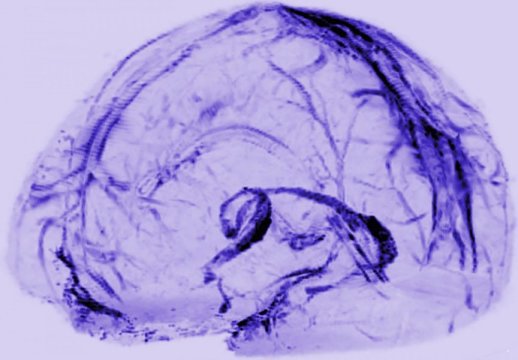

Credit: Reich Lab, NIH/NINDS